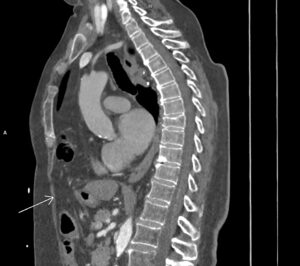

Figurile 1 şi 2: sagital CT în timp venos torace şi abdomen superior

Discuţie caz nr 127: se evidențiază hernierea intratoracică a jumătății distale a colonului ascendent, unghiului hepatic al colonului și a unei părți din colonul transvers printr-un orificiu herniar situat anterior de partea dreapta împreună cu o parte din mezocolon.

DE LUAT ACASĂ!!! Hernia Morgagni este una dintre herniile diafragmatice congenitale și este caracterizata de hernierea prin foramenul Morgagni. În comparație cu herniile Bochdalek, herniile Morgagni tind să fie: localizate anterior, mai des pe partea dreaptă ( aproximativ 90%), mici, rare aproximativ 2% din herniile diafragmatice congenitale), cu risc scăzut de prolaps.